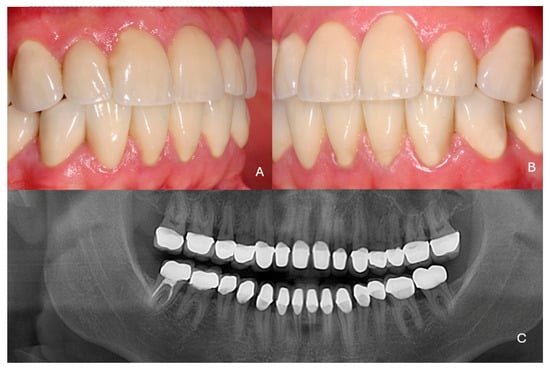

Full Mouth Rehabilitation with All-Ceramic Restorations in a Patient with Amelogenesis Imperfecta: A Case Report with 10-Year Follow-Up

2. Case Presentation